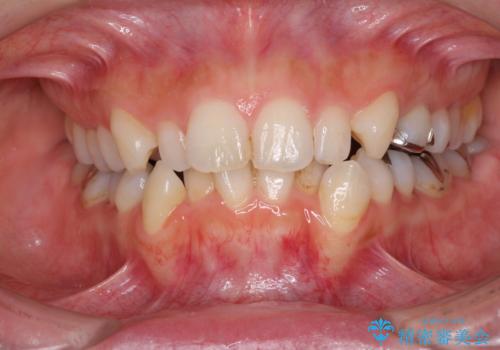

- 前歯のデコボコと矮小歯、更には痛みを感じる奥歯のむし歯を気にして来院された患者様です。

奥歯には根管治療が必要な歯があり、上顎側切歯は左右ともに矮小歯でした。

上下前歯のデコボコはワイヤーでもインビザラインでも対応可能でしたが、補綴治療が多く必要となることから、インビザラインでの矯正治療を行いながら、並行して補綴治療を行うこととしました。

まずは根管治療を行った上で矯正治療用の仮歯を装着し、矯正治療後半に補綴治療を並行して行うこととしました。